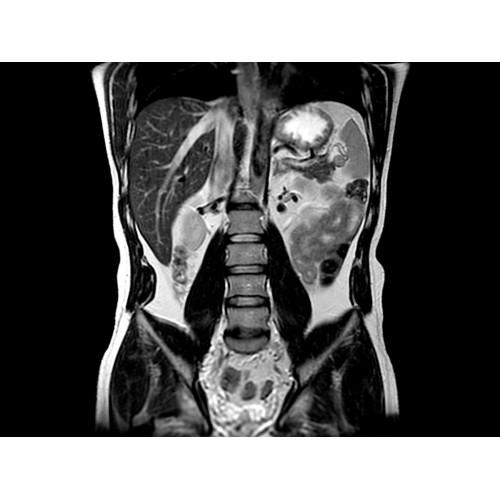

МР-эластография: неинвазивная методика комплектной оценки печени

Пациентам с такими хроническими заболеваниями печени, как фиброз и цирроз, часто требуется регулярное наблюдение гастроэнтеролога. Это может потребовать проведения инвазивных процедур, которые не всегда позволяют получить полную информацию о состоянии печени.

Новая ИП MR-Touch, разработанная компанией GE совместно с клиникой Майо, основана на исследовании печени с помощью акустических волн, в ходе которого выявляются различия в жесткости тканей. Результатом исследования является эластограмма, полное изображение печени. По таким эластограммам радиологи и гастроэнтерологи могут периодически контролировать состояние пациента и принимать информированные решения о терапии. Более того, данная методика открывает новые возможности и позволяет оказывать инновационные услуги имеющимся пациентам и привлекать новых клиентов.